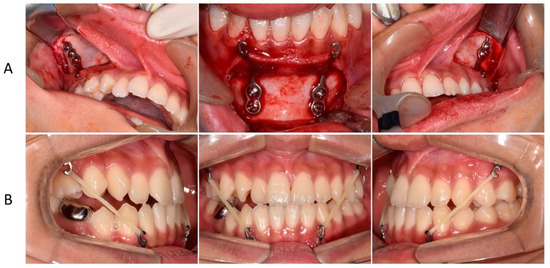

3. Treatment Progress

First, we referred the patient to the oral and maxillofacial surgery department for the extraction of the impacted tooth and placement of the miniplate. The miniplates were placed under general anesthesia. The maxillary plate was placed below the zygoma so that the hook was located between the second premolar and first molar (Figure 3A). In addition, the miniplate was placed in the symphysis area so that the hook was located between the lateral incisor and the canine. A wafer device was worn by the patient for 1 week after surgical extraction of the impacted tooth. For 11 months, the patient wore Class III intermaxillary elastics daily (Figure 3B).

Figure 3. Insertion and use of the miniplate: (A) surgery for miniplate insertion; (B) use of Class III inter-maxillary elastics.